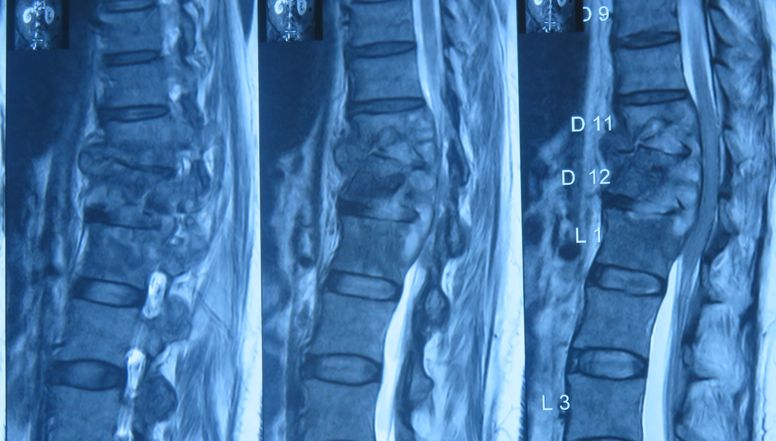

Diagnosis

MRI scan is the most accurate method to detect infection early. Blood tests and CT-guided biopsy help identify the exact organism.